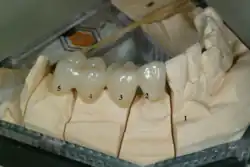

Retentionsform

Zur Verwertbarkeit eines Zahnes und zu dessen Pfeilerwertigkeit gehört, eine Retentionsform durch Zuschleifen (Präparation) des Zahnes herzustellen. Der Halt einer Krone an einem Zahn wird nicht allein durch das Befestigungsmaterial erreicht. Zusätzlich muss eine leicht konische Form (5°- bis 8°-Konuswinkel) für eine Retention der Zahnkrone sorgen.[29] Ebenso ist die Größe der Retentionsfläche maßgeblich für den Halt einer Krone. Ist ein Zahn zu stark zerstört oder wurde bereits bei einer früheren Präparation zu konisch gestaltet oder ist der Kronenstumpf zu kurz, dann sinkt die Pfeilerwertigkeit erheblich.[30] Es besteht insbesondere im Bereich der Molaren die Gefahr, dass sich die Krone vom Zahn löst. Die Gefahr ist im Unterkiefer besonders groß, da einerseits der Zahnersatz starr ist, andererseits der Unterkieferkörper sich bei der Mundöffnung und bei Belastung verwindet. Die Befestigung der Krone am Zahn muss dieser Kräftedifferenz dauerhaft widerstehen können. Die kontrahierten Musculi pterygoidei laterales (äußere Flügelmuskeln) stauchen den Unterkieferbogen mit der mandibulären Symphyse als Fixpunkt, wodurch sich der Unterkiefer um 0,1 bis 1,0 mm verformen kann.[31]